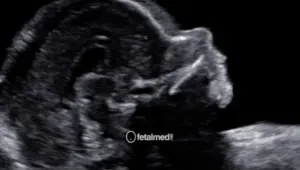

A cardiotocografia (CTG) é um exame que registra simultaneamente os batimentos cardíacos fetais e as contrações uterinas. É um dos principais métodos de avaliação do bem-estar fetal no terceiro trimestre da gestação.

O exame é simples, não invasivo e indolor. Sensores são colocados no abdômen materno e o registro é realizado por 20 a 40 minutos.